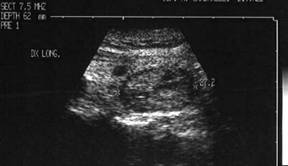

Lob drept , proiectie longitudinala si trasversala .

Barbat de 44 ani. Nodul mare in lobul drept si istm de 31x44x44mm, (30 cc) cu contur net, hipoecogen, neomogen, cu macrocalcificare.

Examn citologic: neoplazie oncocitara (a c. Hurthle).

Examen histologic postoperator: adenom cu celule Hurthle.